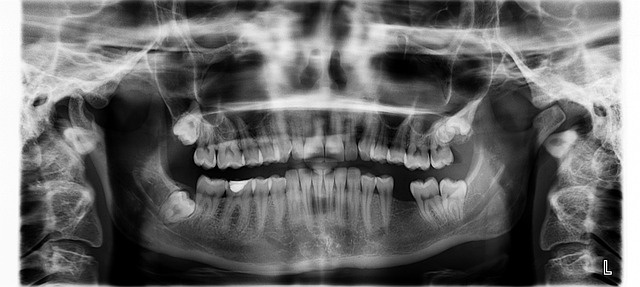

사랑니는 일반적으로 17세에서 25세 사이에 나는 마지막 어금니입니다. 보통 위쪽과 아래쪽 각각 두 개씩 총 네 개가 있습니다. 하지만 사람에 따라 턱 공간이 부족하여 나지 않거나, 매복(치아가 잇몸 안에서 자라난 것)되어 날 수도 있습니다.

혹시라도 볼살이 너무 없어서 예쁘게 난 사랑니만이라도 보전하고 싶거나, 나중에 스페어의 용도로 사랑니를 쓸 수 있지 않을까 하는 아쉬움이 있는 분들은 치과 전문의에게 어떻게 하면 좋을지 상담을 받아보시는 것을 추천드립니다. 제가 어제 받은 상담에서는 제 사랑니가 오른쪽 위아래에 모두 곧게 예쁘게 나 있지만, 안쪽이 잘 닦이지 않아 약간의 충치가 발생하려고 하고 있고, 어쨌든 나중에는 발치하는 게 좋다고 하시면서 발치를 권유하셨습니다.